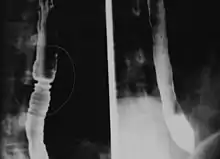

Radiologically, the term "ringed esophagus" has been used for the appearance of eosinophilic esophagitis on barium swallow studies to contrast with the appearance of transient transverse folds sometimes seen with esophageal reflux (termed "feline esophagus").[12]

Endoscopically, ridges, furrows, or rings may be seen in the esophageal wall. Sometimes, multiple rings may occur in the esophagus, leading to the term "corrugated esophagus" or "feline esophagus" due to similarity of the rings to the cat esophagus. Presence of white exudates in esophagus is also suggestive of the diagnosis.[13] On biopsy taken at the time of endoscopy, numerous eosinophils can be seen in the superficial epithelium. A minimum of 15 eosinophils per high-power field are required to make the diagnosis. Eosinophilic inflammation is not limited to the esophagus alone, and does extend through the whole gastrointestinal tract. Profoundly degranulated eosinophils may also be present, as may micro-abscesses and an expansion of the basal layer.[3][10]